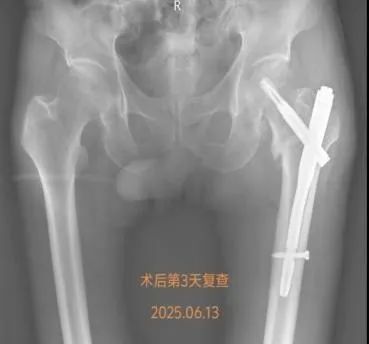

在何流教授的指导下,骨外科主治医师王亮利用C臂机精准引导通过31-2厘米的小切口完成骨折复位与固定手术50分钟,过程顺利,术中出血量仅50毫升

术后,还对戴爷爷进行了康复早期介入。术后第一天,开展了踝关节屈伸训练第三天,借助翻身枕进行侧卧位交替,有效预防压疮形成。